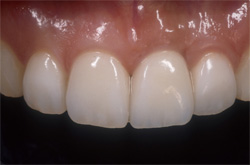

| 失った部分にインプラントを1本埋入します。従来は健全な両隣の歯を削ってブリッジを用いて治療していましたが、インプラントを用いると健全な歯を削ることなく治療を行うことが出来ます。 |

| インプラントの上のクラウンにより、あなたの咀嚼機能と自然な風貌が回復するでしょう。 |